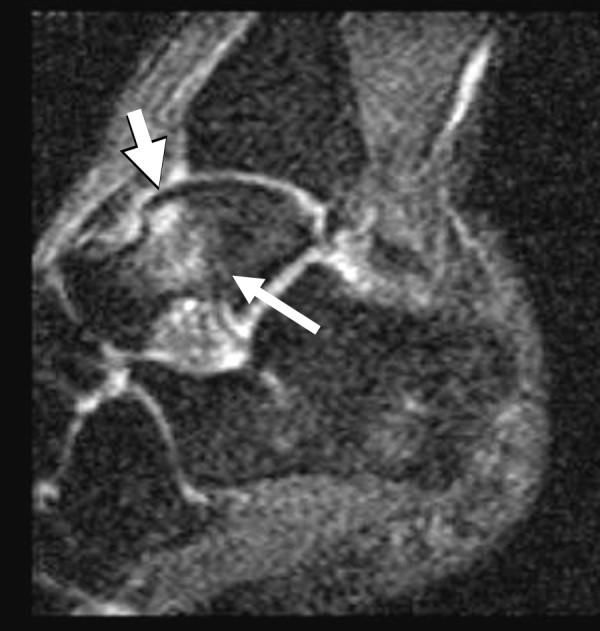

Bone marrow edema was seen only in the talus, and was a common finding, observed in nine of the twelve ankles imaged (75%) and was associated with pain in all cases. On fluid-sensitive sequences, bone marrow edema was ill-defined and centered in the talar neck or body, although in three cases it extended to the talar dome. No apparent gender predilection was noted. No occult stress fracture could be diagnosed. A moderately strong correlation (phi = 0.77, p= 0.0054) was found between edema and pain in the study population.

仅在距骨中发现骨髓水肿,这是一个常见的表现,在12个成像踝关节中的9个(75%)观察到,并且在所有病例中均与疼痛相关。在液体敏感序列上,骨髓水肿边界不清,集中在距骨颈或距骨体,尽管在3例中延伸至距骨穹窿。未发现明显的性别倾向。未诊断出隐匿性应力性骨折。在研究人群中,水肿与疼痛之间存在中度强相关性(phi = 0.77,p = 0.0054)。